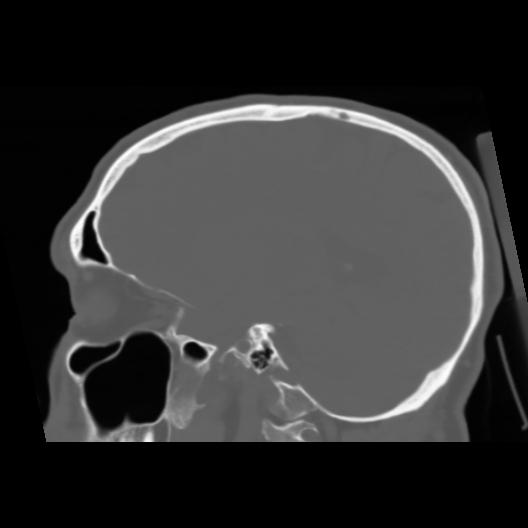

6 CEREBRO,,Sagittal,3.000,CEREBRO,Sagittal,